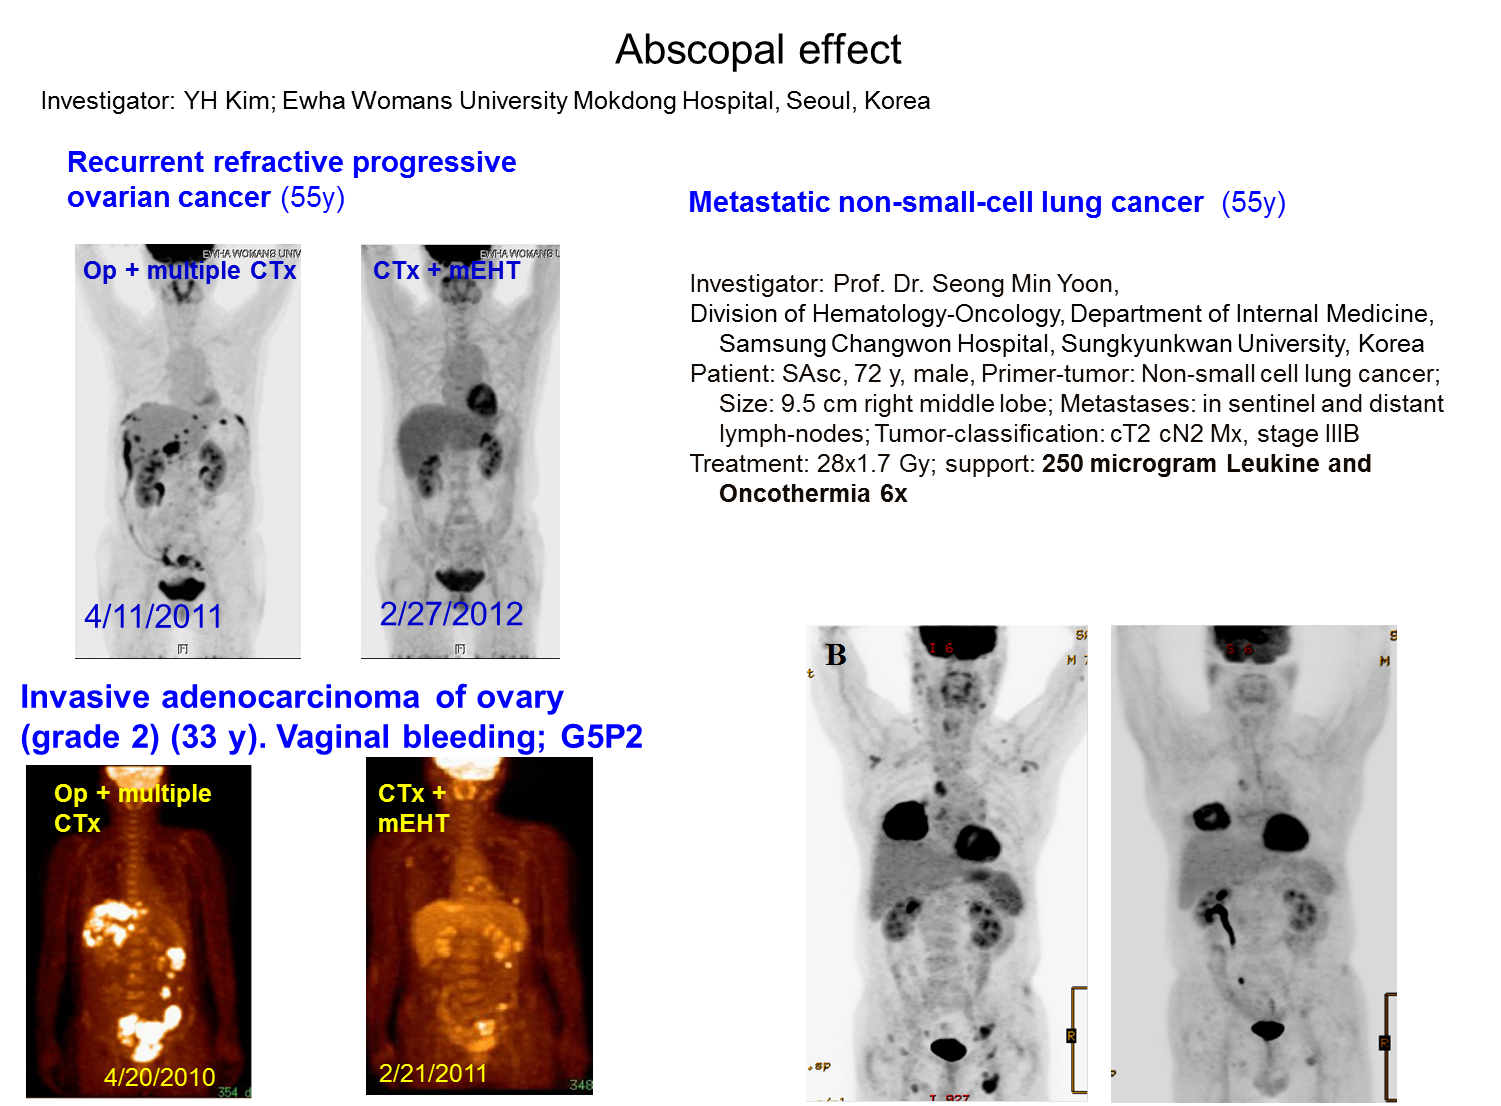

奈米電熱治療形成的遠端效應 (Abscopal Effect)

Abscopal effect, 中文叫隔山打牛。聽起來很有趣,實際上卻是癌症治療的最高成就。它的意思是治療主要的癌症部位時,其他未接受治療的轉移腫瘤也一併消失。是癌症末期時,醫師最希望在病人身上看到的治療效果。一旦發生,表示病人很有機會從末期變成痊癒。在以往的十多年間,只要發現一個這樣的神奇病例,就可以發表個案報告的文章在國際期刊上。因為十分罕見,大概一年只有一個案例在國際上發表。近期我們在新光醫院的奈米電熱治療案例中進行統計,很驚訝地發現新光醫院一年來進行安可勝奈米電熱治療竟然有三例癌症末期的病友發生隔山打牛的神奇現象。今年在德國的歐洲熱療大會,南非的米爾醫師也發表他們的團隊所進行的安可勝奈米電熱治療在子宮頸癌的臨床試驗,有15%的病人發生隔山打牛的現象。由此可見,安可勝奈米電熱治療是引發隔山打牛這個癌治療最高成就的有效武器。